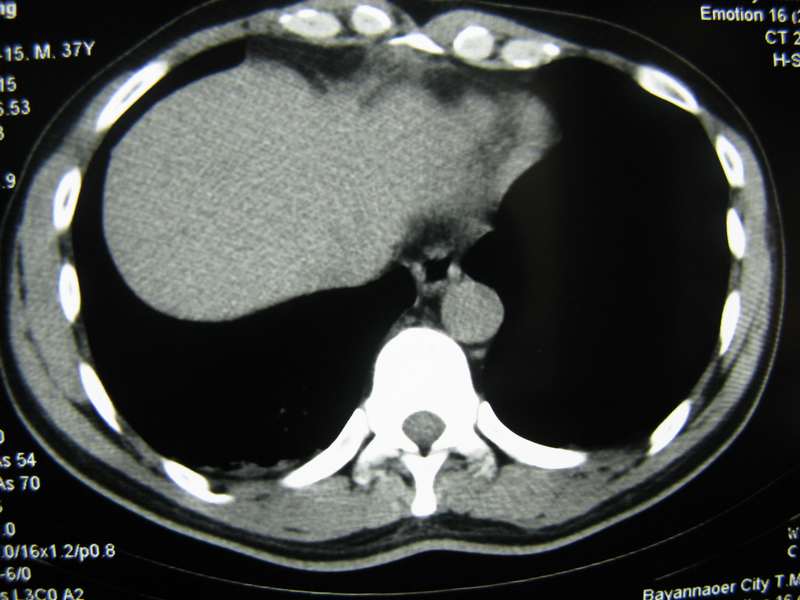

男,37岁,主述胸疼厉害,无咳嗽,无发热,血象也不高,病灶内ct值脂肪密度,右侧胸腔内少量积液,同道们考虑什么?谢谢!

两肺下叶基底段纤维灶,右肺下叶基底背侧相应胸膜肥厚,右肺中叶内侧段部分不张。前中下纵隔团块状脂肪影,随访除外胸腺脂肪瘤。

不除外膈疝。